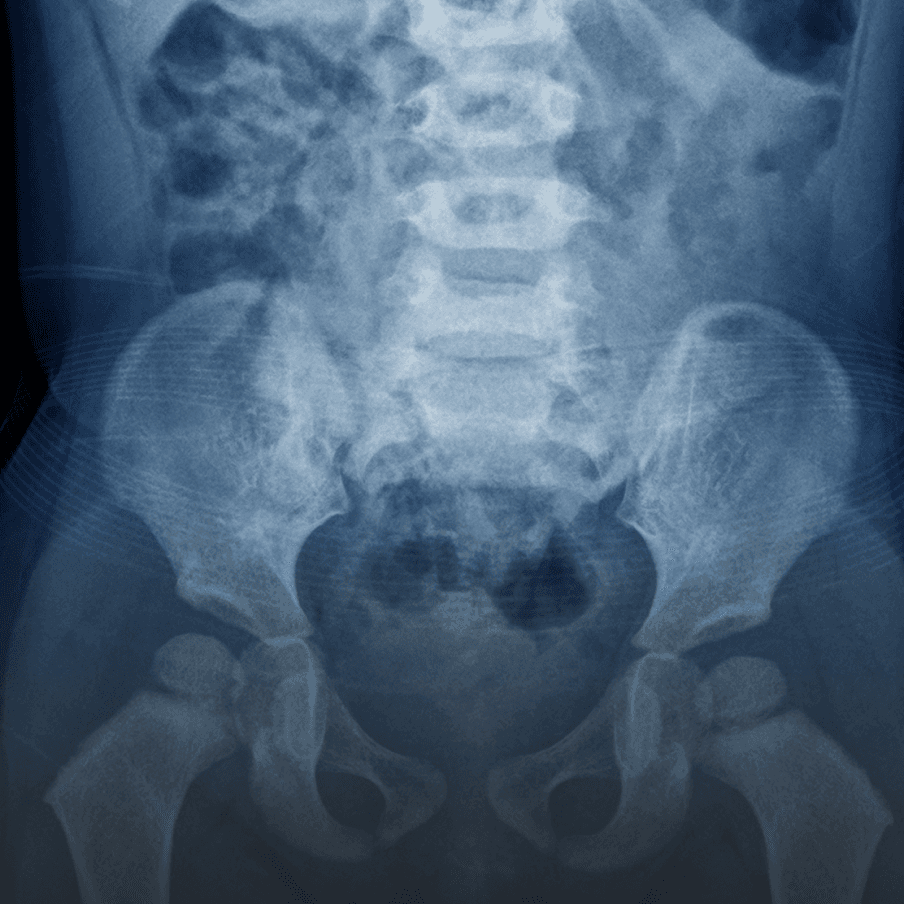

Abdominal X-ray

A non-invasive way to visualize the organs in the abdominal cavity, helping to diagnose issues like blockages or kidney stones